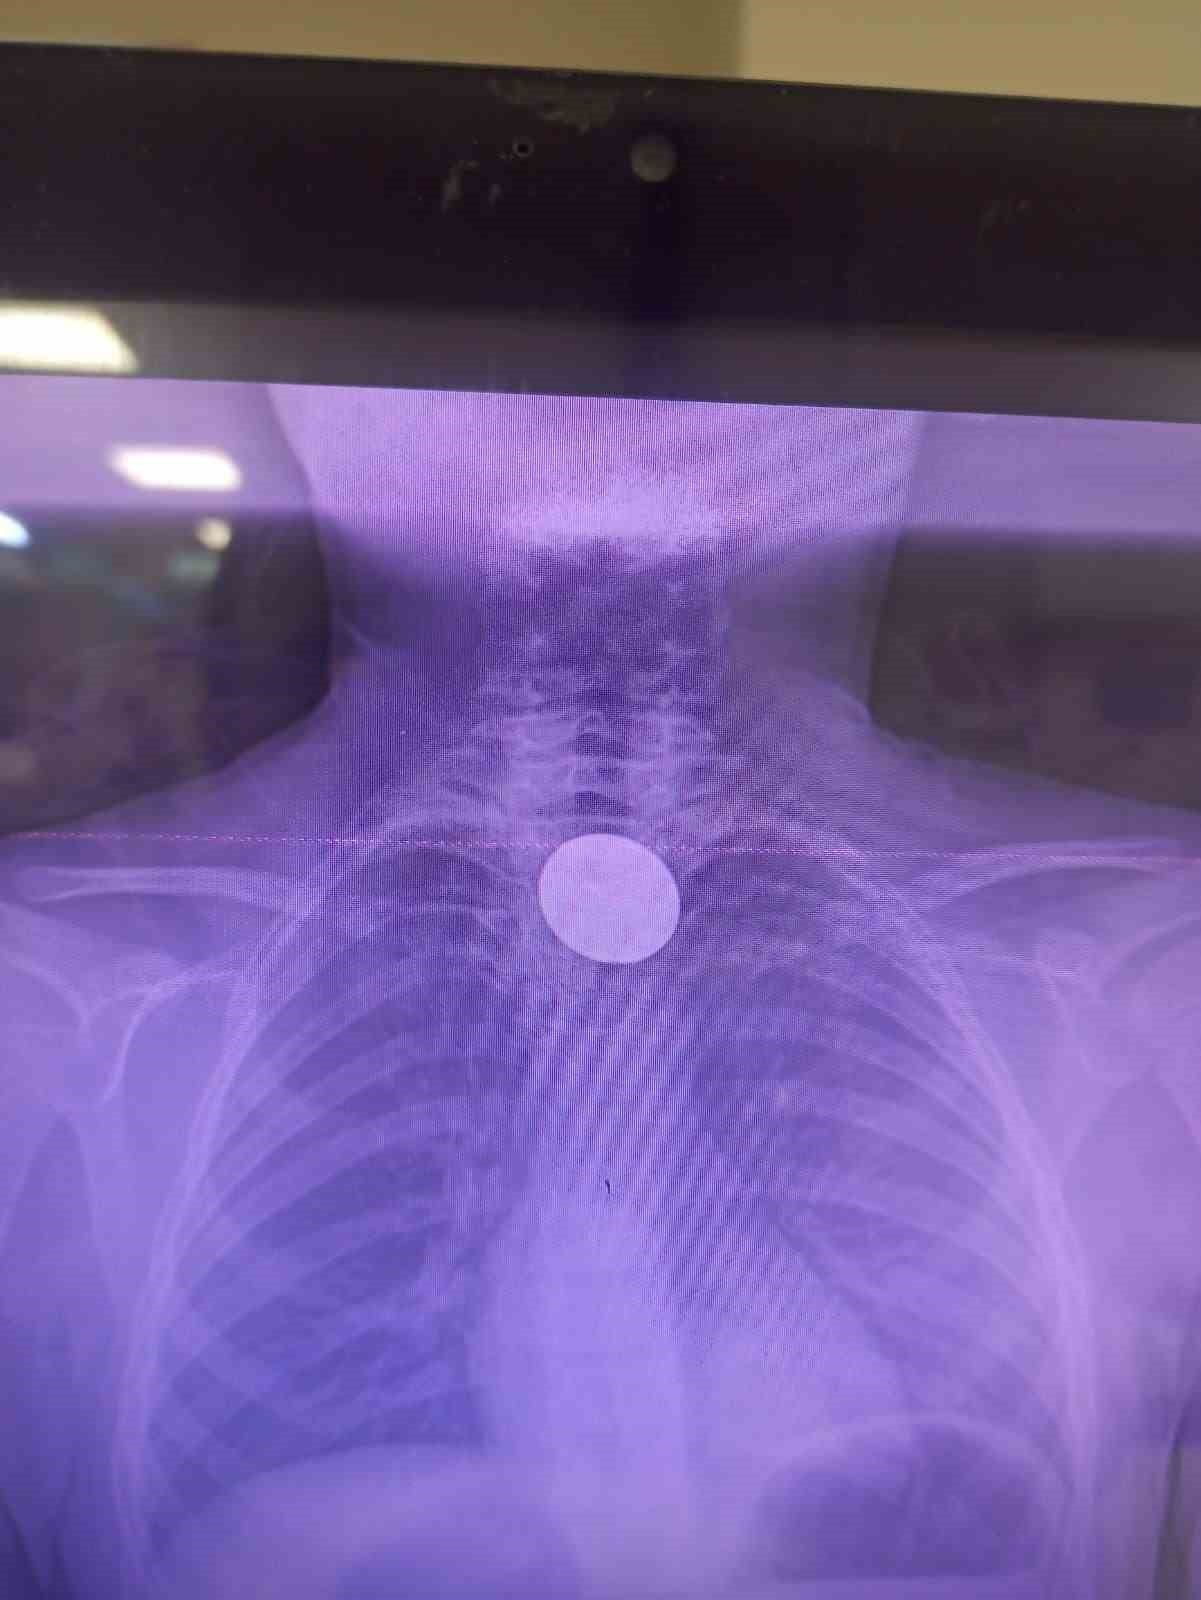

Siirt Eğitim ve Araştırma Hastanesi'ne ailesi tarafından getirilen 8 yaşındaki Y.K., yabancı cisim yutma şikayetiyle acil serviste değerlendirildi. Yapılan görüntüleme ve ilk incelemeler sonucunda madeni paranın yemek borasına kadar ilerlediği tespit edildi.

Gastroenteroloji uzmanı Dr. Yaren Dirik ve kulak burun boğaz hekimi Yasin Gökçınar tarafından ortaklaşa yapılan müdahalede, boğaza kaçan 5 lira çıkarıldı. Operasyonun ardından çocuk bir süre gözlem altında tutuldu ve tedavisi tamamlandıktan sonra taburcu edildi.

Siirt Eğitim ve Araştırma Hastanesi Başhekim Yardımcısı Uzman Dr. Burak Özkan konuyla ilgili olarak, "Hastanemize başvuran 8 yaşındaki hastamızın yemek borusuna kaçan madeni para, gastroenteroloji ve KBB ekiplerimizin koordineli ve titiz çalışmasıyla herhangi bir komplikasyona yol açmadan başarılı bir şekilde çıkarılmıştır. Operasyon süreci sorunsuz geçmiş olup hastamızın genel durumu iyidir" dedi.